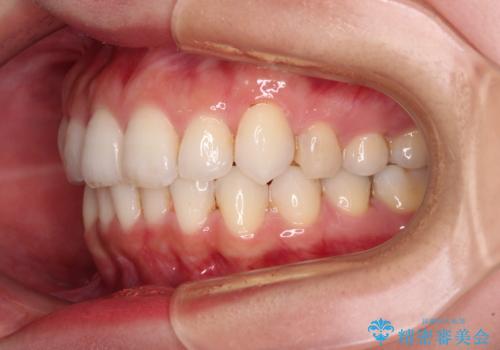

1日22時間の装着時間を守ってくださったので、比較的早く治療を終える予定でしたが、各国での入国制限が厳しくなり、帰国のタイミングに合わせてのんびりと治療を進めることとなってしまい、やや長期間の治療となりました。